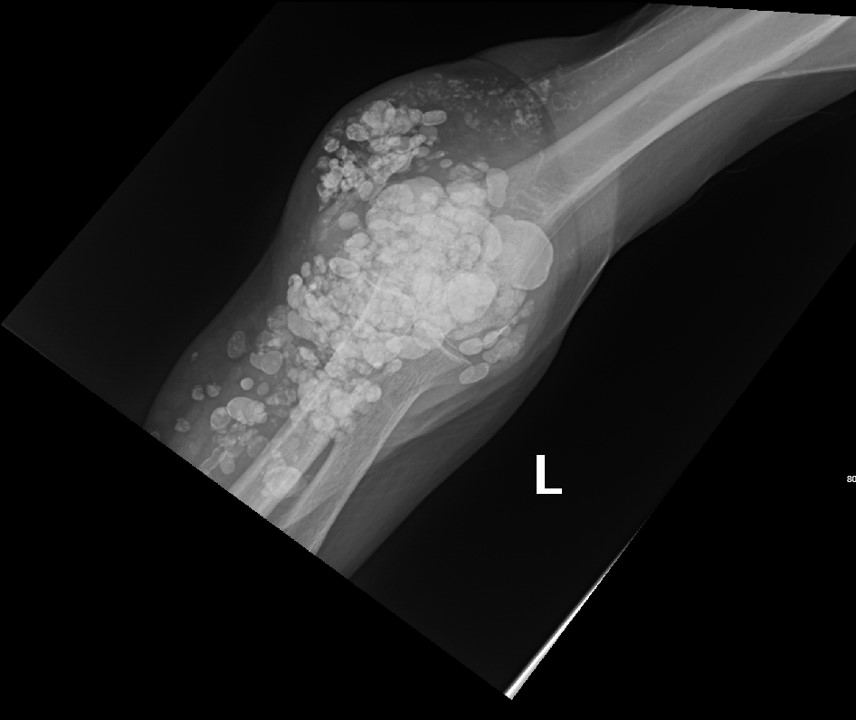

Calcinosis cutis is a condition in which calcium-phosphate salt deposits are formed in cutaneous and subcutaneous tissue. A subtype, metastatic calcinosis cutis, can occur in patients with disorders that cause hypercalcemia or hyperphosphatemia such as end stage renal disease. We present a case of a 67-year-old man with end-stage renal disease (ESRD) on dialysis who presented to the emergency department with a draining left elbow wound. On exam, he had irregular, firm nodules palpable in the subcutaneous tissue of both large and small joints. The presence of calcinosis cutis on imaging and lack of other findings suggesting infection led to outpatient wound care treatment. Recognizing the appearance of calcinosis cutis on imaging and conditions that present with calcinosis cutis is important for the emergency physician.

Topics: Calcinosis cutis, end-stage renal disease, ESRD, dialysis, subcutaneous calcifications.